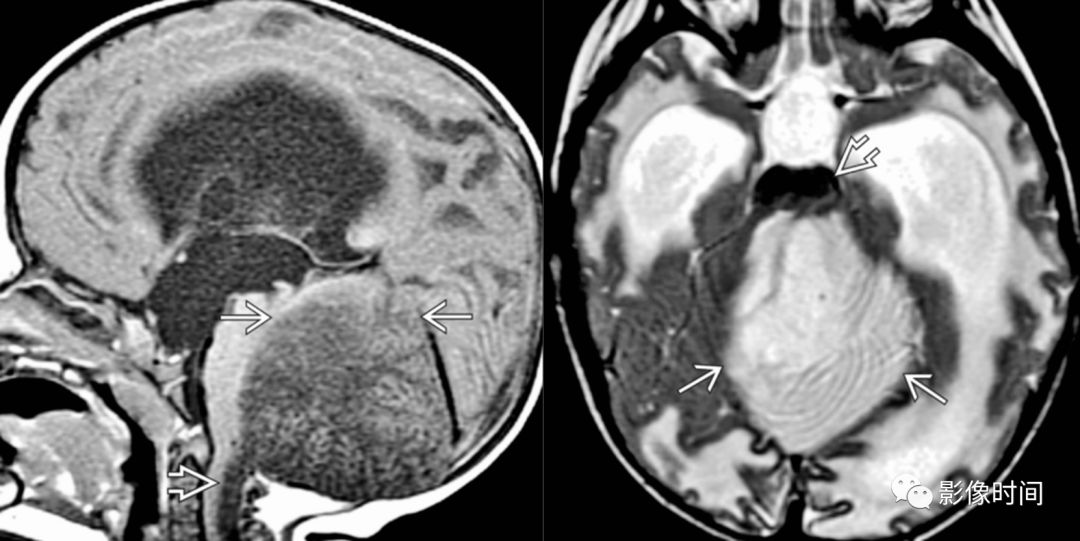

上行小脑幕切迹疝小脑半球占位导致上行小脑幕切迹疝,小脑半球跨越

图片尺寸1080x541